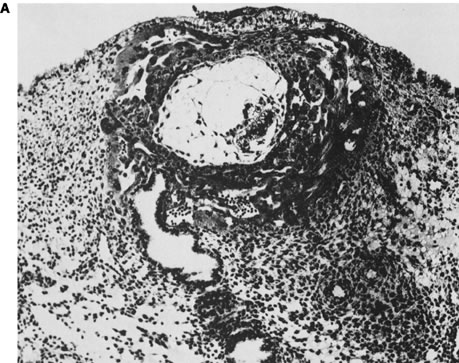

BeSt programmi toetusel valminud õpiobjekt "Korduv raseduse katkemine" on koostatud eesmärgiga anda sünnitusabi ja günekoloogia eriala spetsialistele, doktorantidele ja residentidele kaasajastatud ülevaade igapäevases kliinilises töös suhteliselt sageli esinevast probleemist. Õppematerjal koosneb nelja haigusjuhu analüüsist ja teoreetilisest osast, kus käsitletakse korduva raseduse riskitegureid, põhjusi ja ravi võimalusi. Õppematerjal sisaldab mitmeid testivormis küsimusi, mille abil saab hinnata oma teadmisi õppeprotsessi vältel. Kasutatud materjalid ja täiendavad infoallikad on toodud materjali lõpus teemade kaupa. Õppematerjali läbitöötamiseks kulub orienteeruvalt 10-12 tundi.